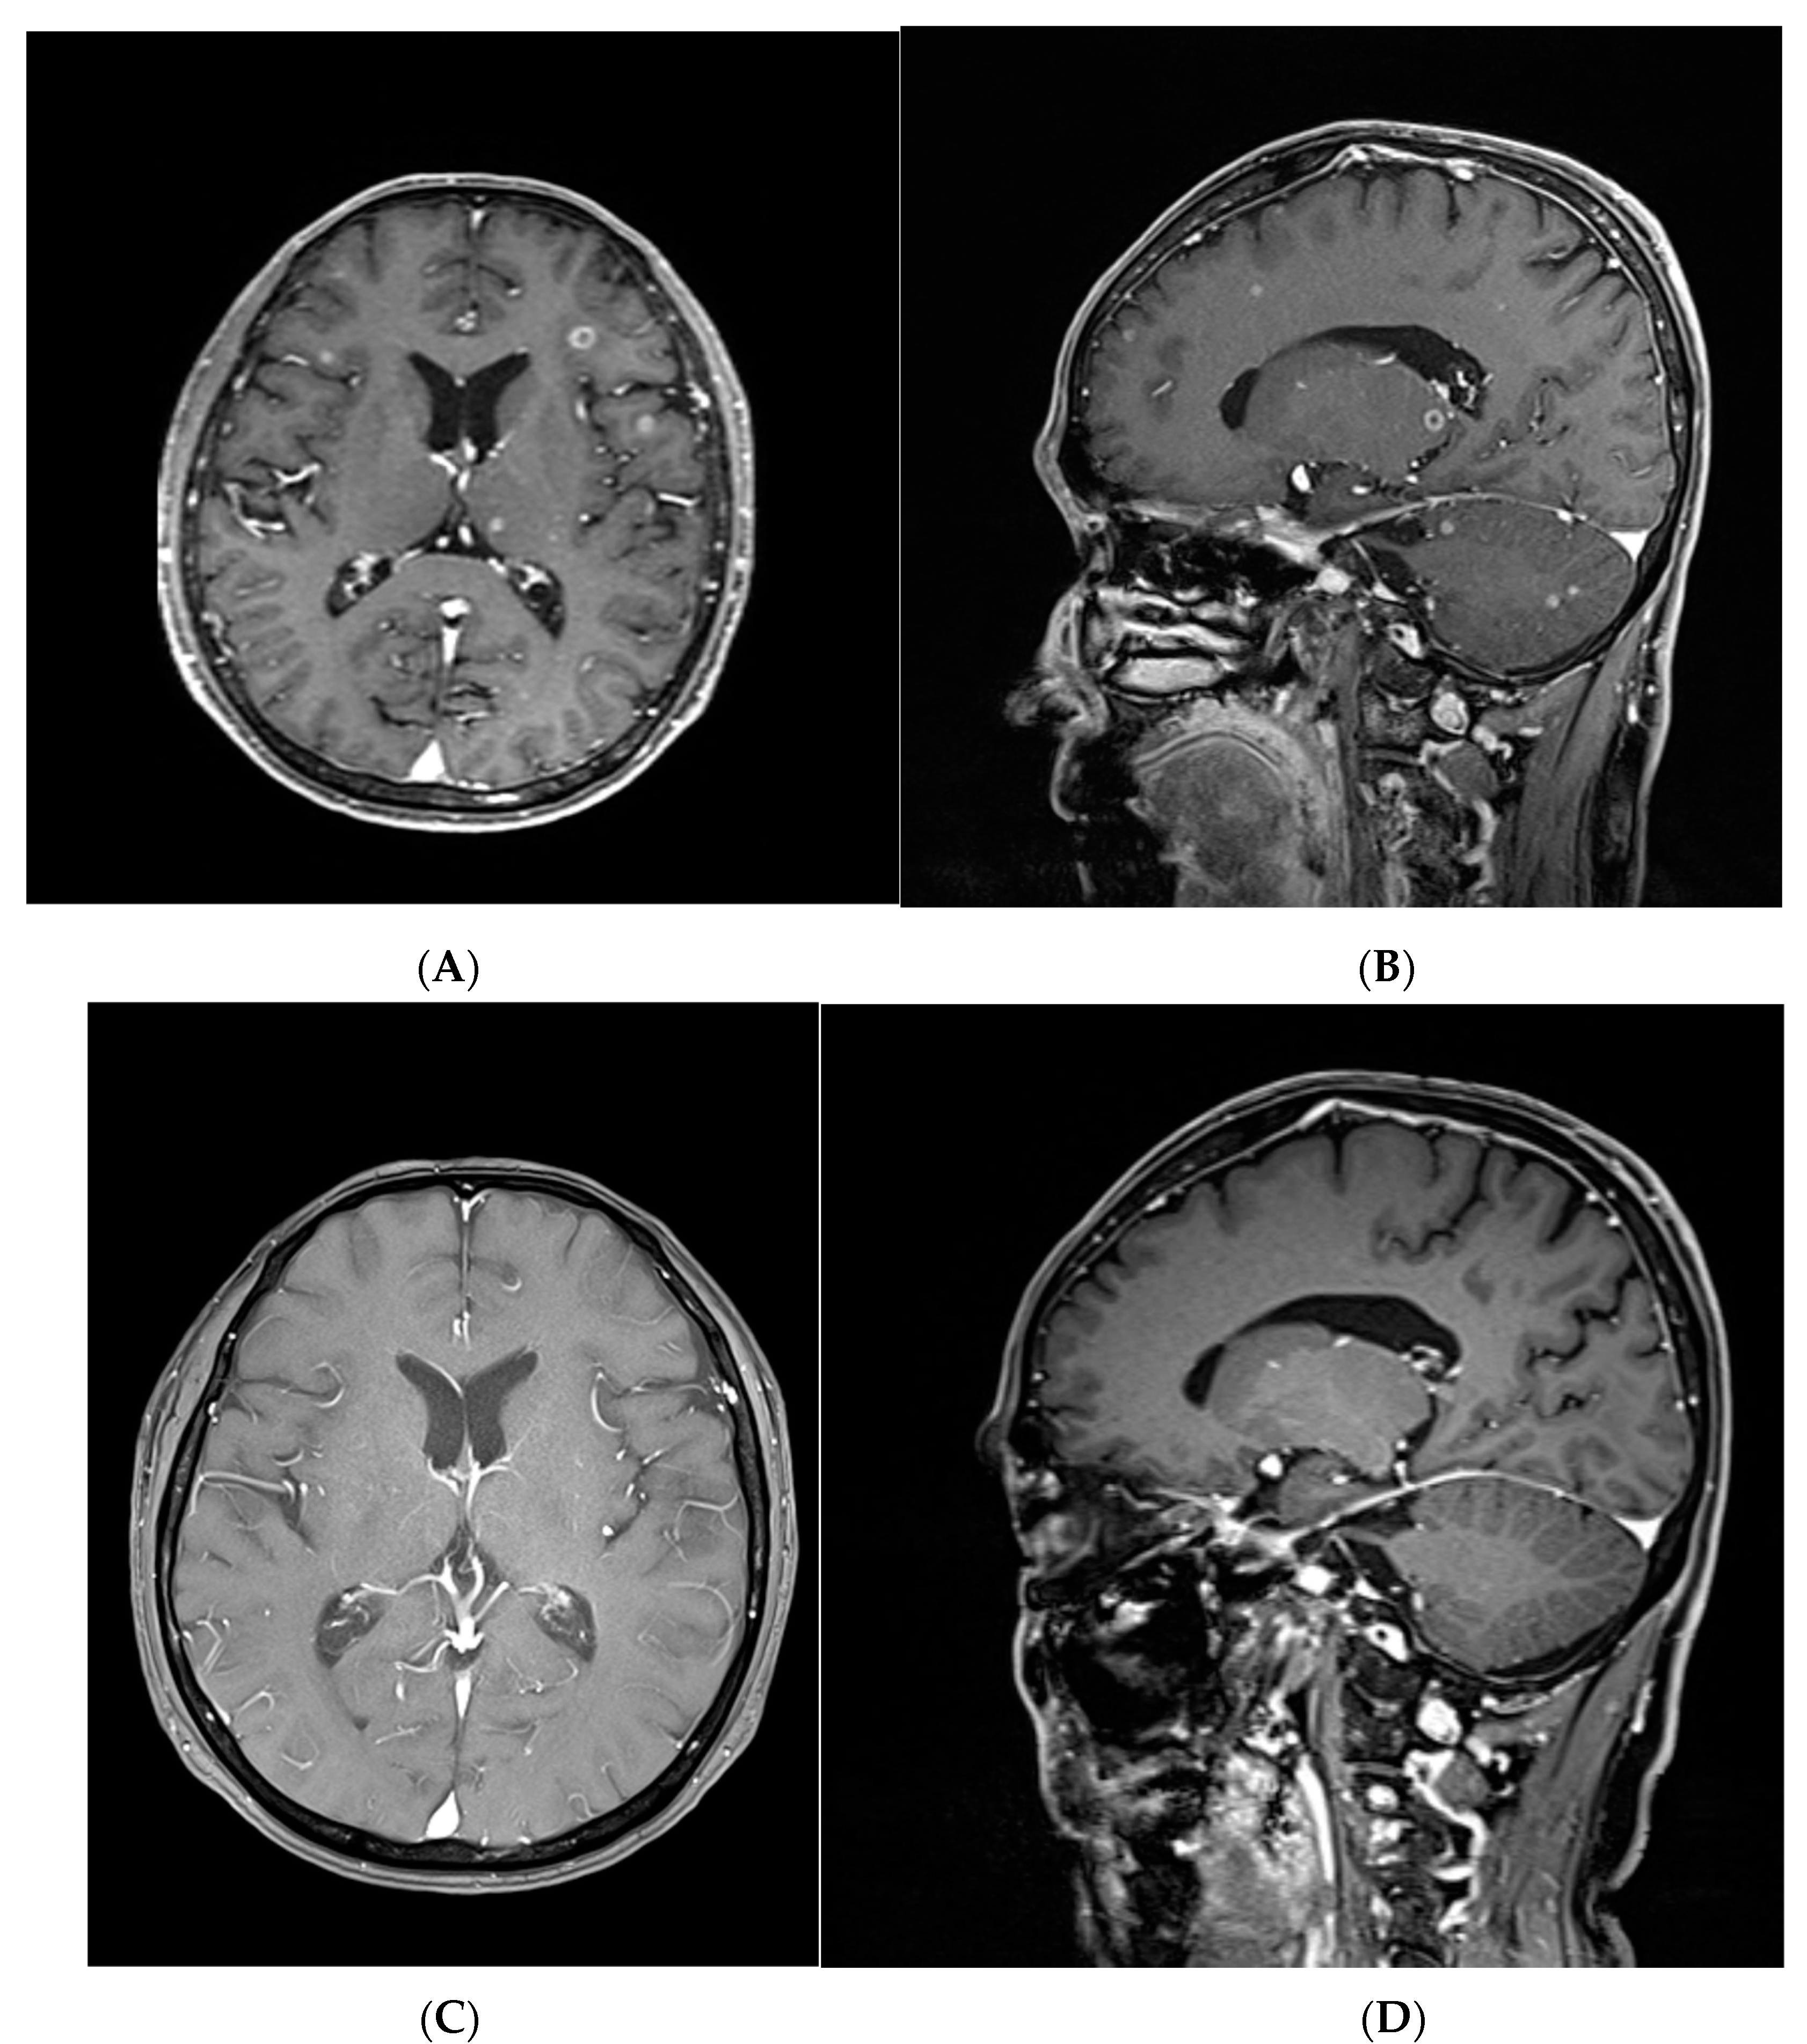

3.5. A Representative Case Treated with Targeted Therapy without Local Brain Treatment